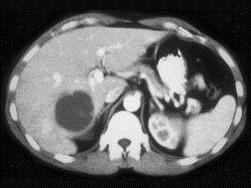

问题 女,58岁,肝区疼痛半月,发热,白细胞升高,CT检查如图,请选择最可能诊断 ( )

选项 A、肝转移瘤 B、肝棘球蚴病 C、肝囊肿 D、肝脓肿 E、原发性肝癌

答案 D